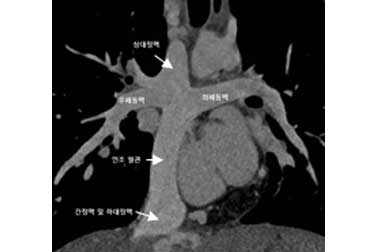

(2) 폰탄수술 후의 CT 소견

폰탄수술 후의 CT 소견